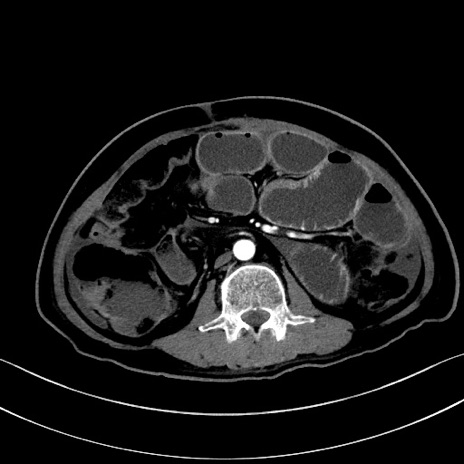

冠状断像

【症例】60歳代男性

【主訴】嘔吐

【現病歴】胃癌にて胃全摘後。食思不振が悪化し、夜中に嘔吐することがある。

【既往歴】胃癌、胃全摘、脾摘、胆摘後

【データ】WBC 5900、CRP 10.56